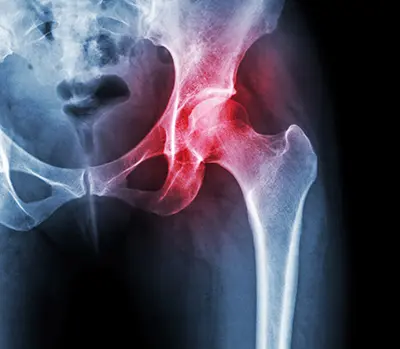

Hip replacement is indicated in patients with arthritis of the hip joint.

Arthritis is a condition in which the articular cartilage that covers the joint surface is damaged or worn out, causing pain and inflammation. Some causes of arthritis include:

Patients with arthritis may have a thinner articular cartilage lining, a narrowed joint space, or bone spurs and excessive bone growth around the edges of the hip joint. These changes can cause pain, stiffness, and restricted movement.

Your doctor will evaluate arthritis based on characteristic symptoms and diagnostic tests. Your orthopedic surgeon will perform a physical examination, order X-rays and other scans, and may order blood tests to rule out other conditions that can cause similar symptoms.